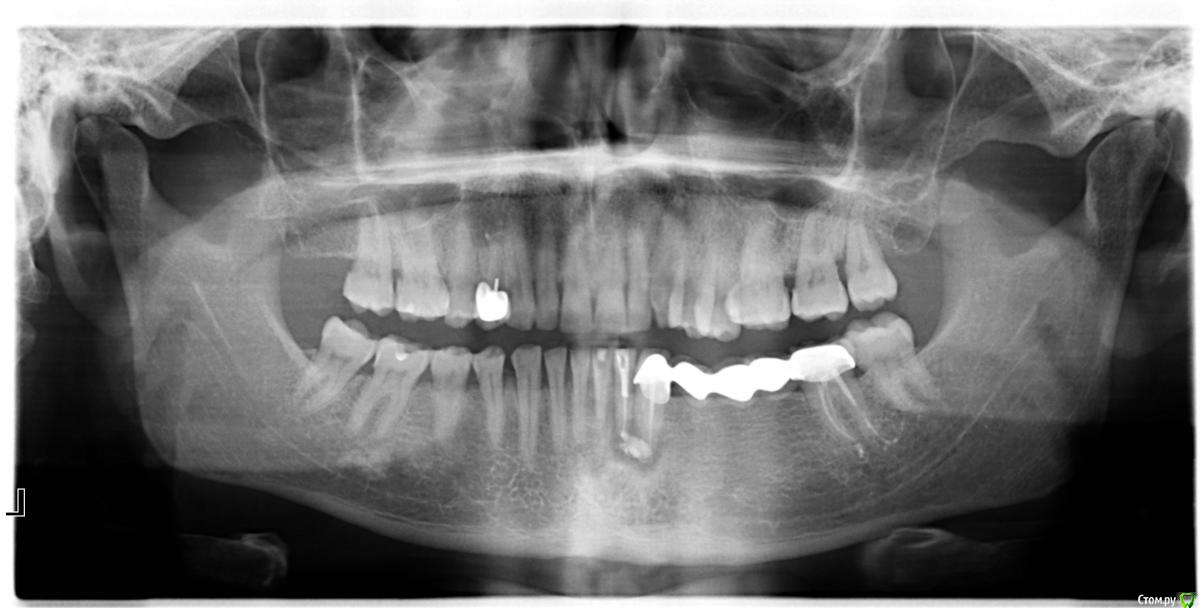

Гранит Опубликовано 13 марта, 2016 Поделиться Опубликовано 13 марта, 2016 Уважаемые стоматологи, прошу совета по имеющейся ситуации.41 зуб беспокоил год назад, его пытались лечить, вложив лекарство в канал. Год проходил без жалоб.Теперь опять стал побаливать, 41 и 42 пошатываются Как мне объяснили под 41, 42 и 43 зубами имеется киста. 43 и 47 являютя опорными для моста- эти зубы меня не беспокоят.Но, тем не менее врач считает что и 43 зуб требует удаления, а соответственно и мост удалять, Иначе в кости будет идти процесс разрушения.Предлагают: мост отпилить оставив коронку на 47 зубе. 41, 42, 43 удалить вместе с основной частью моста. Действительно ли опорный зуб - 43 требуется удалять?Может удалить 41, 42, а мост пока оставить. Или это приведет к дальнейшему развитию кисты?КТ 1.docКТ 2.doc Ссылка на комментарий

red_butler Опубликовано 13 марта, 2016 Поделиться Опубликовано 13 марта, 2016 Если судить только по снимкам, то повторное лечение корневых каналов и цистэктомия. Мост снимать и имплантировать участок где потеряны зубы.И 1.4 зуб перелечивать. 1 Ссылка на комментарий

red_butler Опубликовано 14 марта, 2016 Поделиться Опубликовано 14 марта, 2016 Правильно ли будет провести повторное лечение корневых каналов и провести цистэктомию, как Вы говорите, но мост пока оставить на год-полтора, имплатацию спланировать через год-полтора..протяженность мостовидного протеза такая большая, что перегрузка опорных зубов их скоро доконает, и Вы вылечив одно, удалите клык по другой причине. 3 Ссылка на комментарий